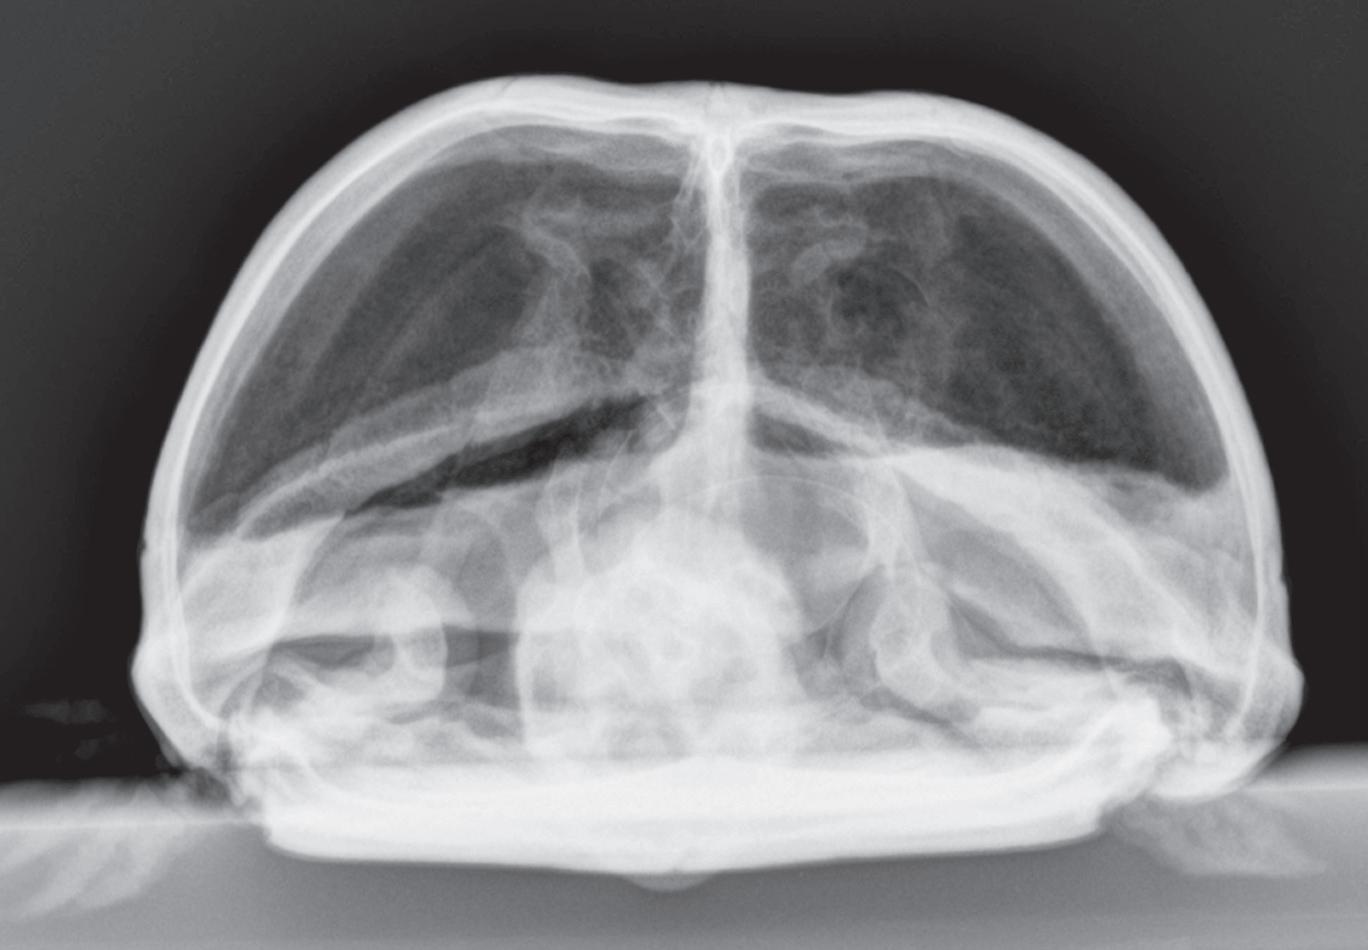

Making the same standard orthogonal views of every body part is very important. Looking at the same radiographic projections and orientations repeatedly makes it easier to recognize abnormal from normal. On the other hand, when an object or body region is radiographed using an unconventional point-of-entrance to point-of-exit of the x-ray beam, the image becomes less recognizable and more diffcult to interpret (Figure 1-6).

Figure 1-6. Dorsoventral (A), lateral (B), and rostrocaudal (C) radiographs of a box turtle. In A and B, which are orthogonal to each other, it is clear that the subject is a turtle. Eggs are visible in the coelom. In C, which is also an orthogonal view with respect to both A and B, it is not obvious that the subject is a turtle because this orientation is uncommon and unfamiliar. The eggs are also not visible in C.